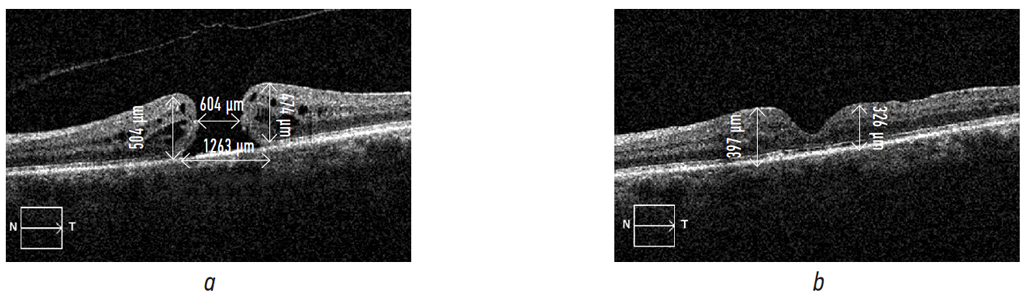

According to the data presented in the table, before surgery, in the overwhelming number of patients (85.8%), visual acuity was from 0.01 to 0.1, during the post-op period, in a significant number of patients (76.8%), visual acuity raised up to 0.2–0.3 and higher. As examples, pre- and postoperative OCT results of patients L. and G. and their visual functions are shown on Fig. 3 and 4, respectively.

Fig. 4. Patient G. Right eye: macular hole stage 4, the macular hole history is about 1.5–2 years: a — Right eye: Vis before surgery 0.08; b — Right eye: Vis after surgery 0.3–0.4

Рис. 4. Пациент Г. Макулярные разрывы правого глаза (OD) IV стадии, длительность существования МР (из анамнеза) около 1,5–2 лет: a — Vis OD 0,08 до операции; b — Vis OD 0,3–0,4 после операции